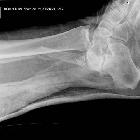

Plain radiograph and CT

- direction of dislocation and associated fractures can be estimated with anteroposterior and lateral radiographs

- medial dislocation: on lateral views, talar head is superior to navicular

- lateral dislocation: on lateral views, talar head is colinear or inferior to navicular